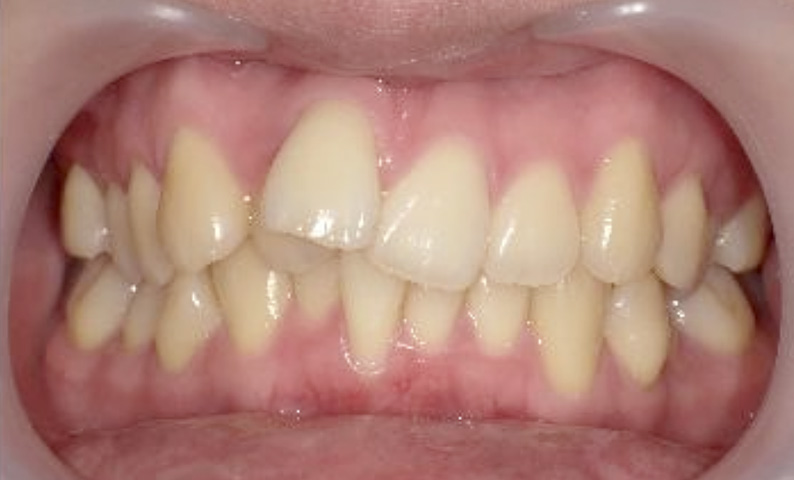

症例_022 上下顎の部分矯正

治療期間:7ヶ月金額:54万円+税女性前歯のガタガタ八重歯一部反対咬合

| Before | After |